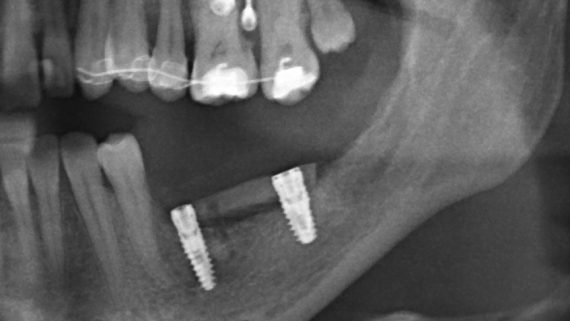

Остеопластические операции: факторы успеха. Часть II.